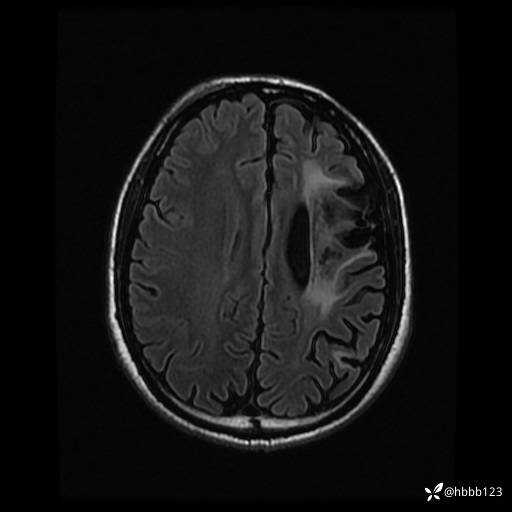

T2 Flair: